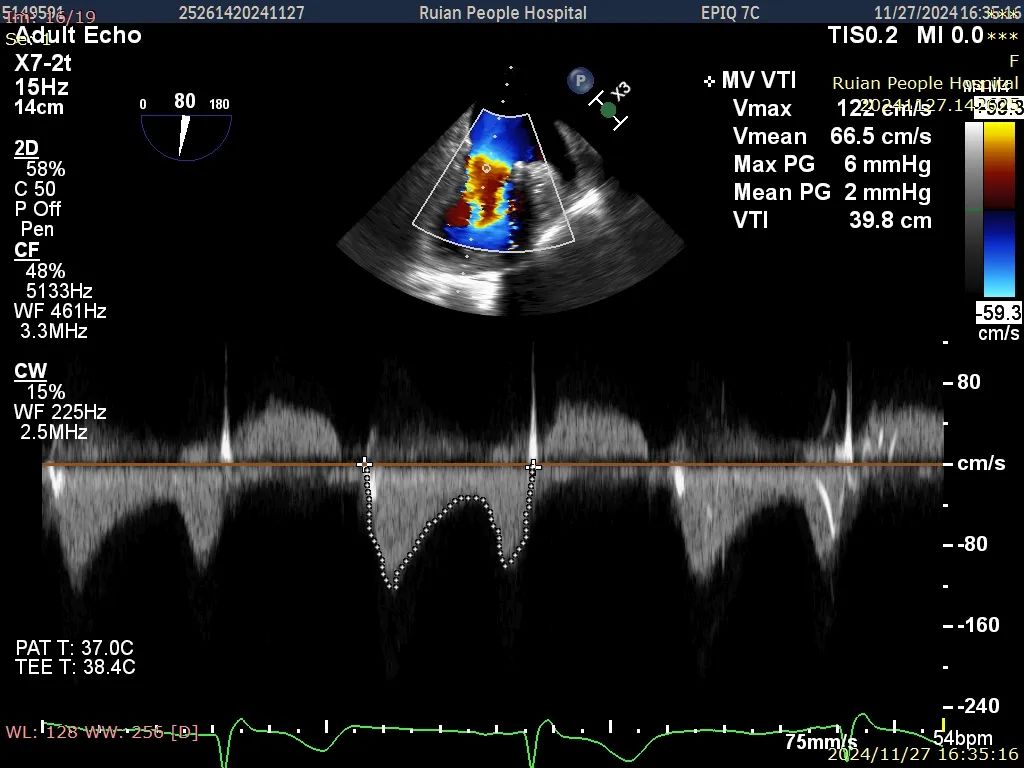

慢性心衰急性加重,呼吸困难,水肿,胸腔积液反复住院,术前经食道心脏超声可见:左心扩大;P1脱垂伴部分腱索断裂,可能累及外交界处,瓣叶连枷样运动;重度DMR(4+);

病变区域瓣叶长度:前叶22mm、后叶13mm、脱垂宽度10mm、瓣口面积4.4。

王永光、潘嘉西教授协同超声科进行全面会诊与讨论,决定应用先进的国产二尖瓣修复利器,行经导管二尖瓣缘对缘修复术。术前与刘先宝、林心平教授通过严密的讨论,决定采用短宽夹子夹解决脱垂并封住交界区,并且在术中关闭二尖瓣夹时注意释放瓣叶张力。术中房间隔穿刺高度3.7cm,于1区偏交界植入一枚短宽夹,夹闭后反流Trace(微量),二尖瓣跨瓣压差2mmHg,肺静脉逆流消失,术毕。

释放后二尖瓣跨瓣压差2mmHg

术中释放后跨瓣压差2mmHg